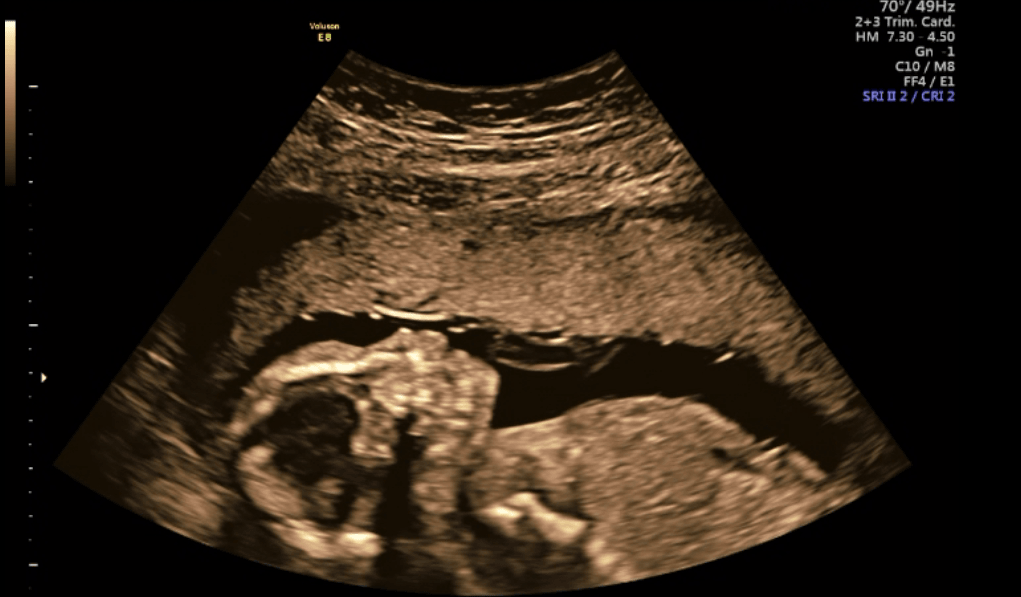

Połówkowe - wyniki

IMG_2235.JPG

Tydzień ciąży wg om 19+6

Tydzień ciąży wg usg 19+5

Waga: 311 g

Tętno: 160 u/min

Płeć: dziewczynka

Narządy prawidłowe